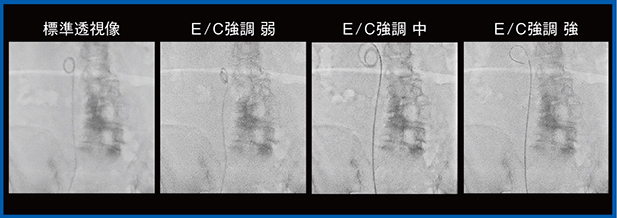

2.尿管ステント交換症例と造影症例

尿管ステント交換症例は,E/C強調の弱の評価が高く(図6),経イレウス管小腸造影検査では,E/C強調の中または強で造影剤の流れが明瞭に確認できた(図7)。

また,体格の大きい患者に対する脊髄腔造影(ミエログラフィ)では,Live像輝度調整に加え,Accentモード(E/C強調)を適用し,線量を上げずに明瞭に視認できた(図8)。

図6 尿管ステント(Accent適用)

図7 経イレウス管小腸造影(Accent適用)

図8 脊髄腔造影(Accent+Live像輝度調整を適用)